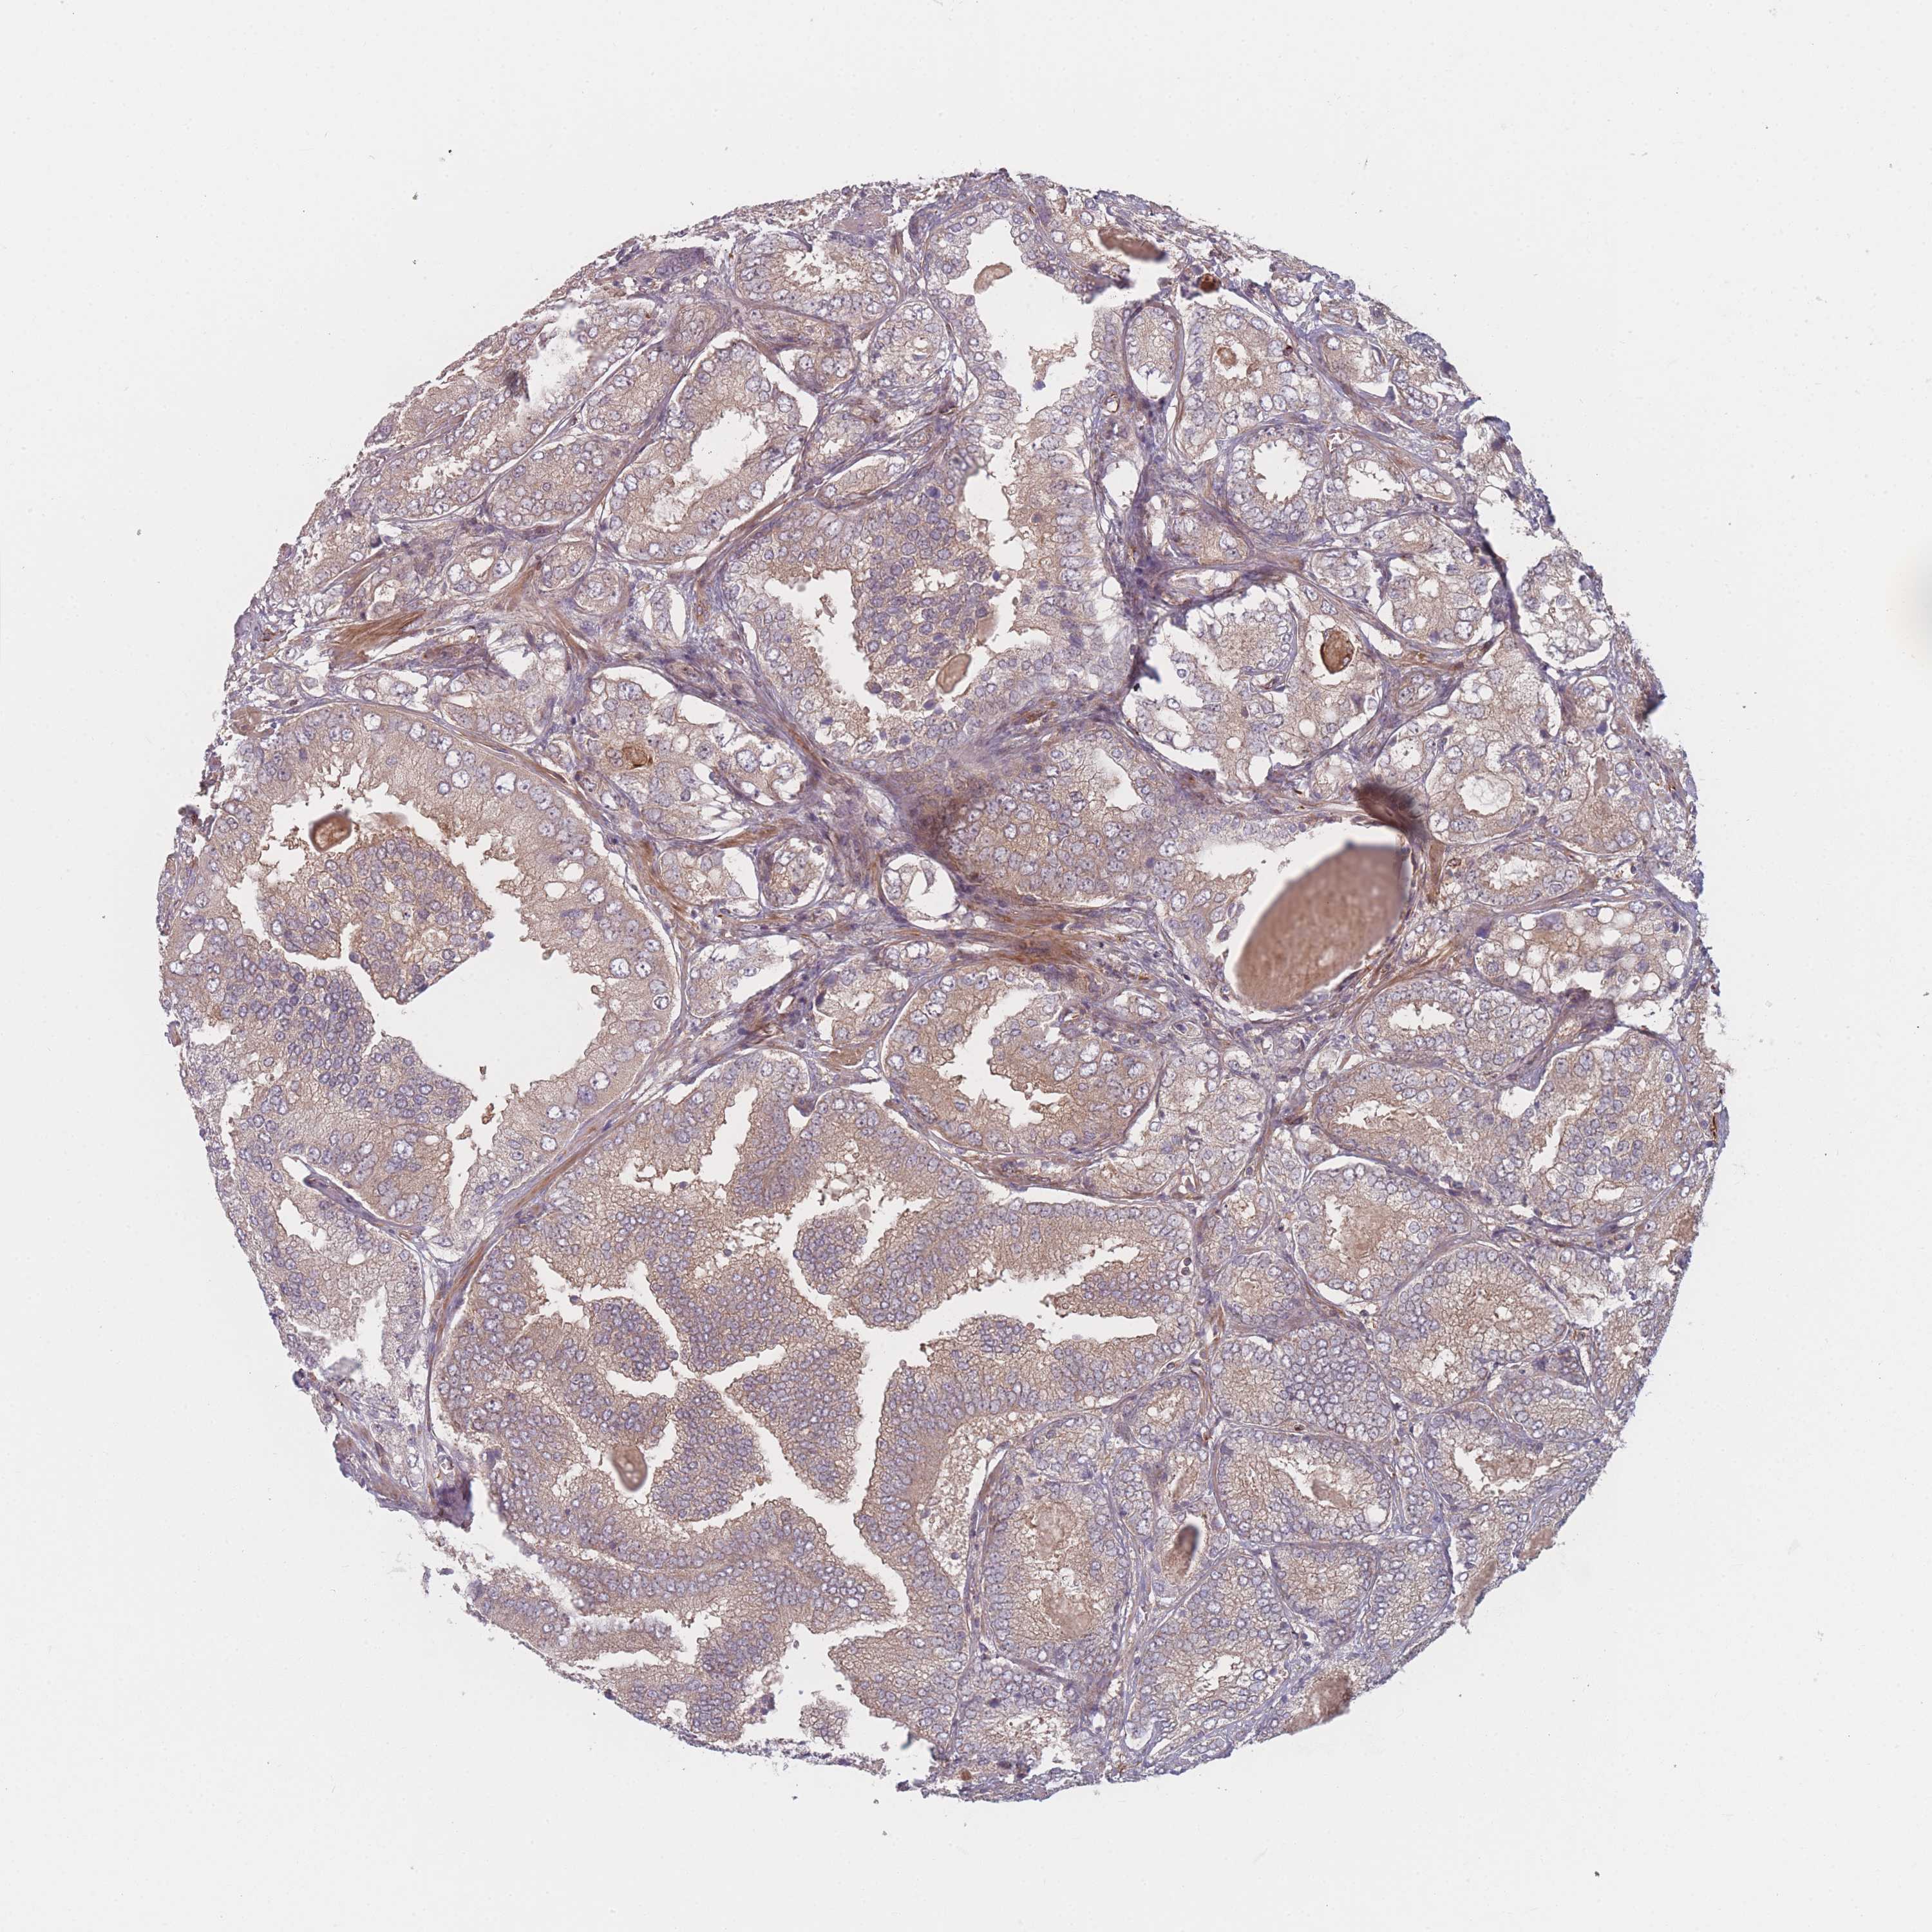

PROSTATE CANCER - Protein expressioni

A mouse-over function shows sample information and annotation data. Click on an image to view it in a full screen mode. Samples can be filtered based on level of antibody staining by selecting one or several of the following categories: high, medium, low and not detected. The assay and annotation is described here.

Note that samples used for immunohistochemistry by the Human Protein Atlas do not correspond to samples in the TCGA dataset.

Antibody stainingi

Antibody staining in the annotated cell types in the current human tissue is reported as not detected, low, medium, or high, based on conventional immunohistochemistry profiling in selected tissues. This score is based on the combination of the staining intensity and fraction of stained cells.

Each image is clickable and will lead to virtual microscopy that enables deeper exploration of all samples and also displays staining intensity scores, fraction scores and subcellular localization as well as patient and tissue information for each sample.

Antibody HPA050138

Staining

High

Medium

Low

Not detected

Intensity

Strong

Moderate

Weak

Negative

Quantity

>75%

75%-25%

<25%

None

Location

Nuclear

Cytoplasmic/membranous

Cytoplasmic/membranous,nuclear

Adenocarcinoma, High grade

Adenocarcinoma, Low grade